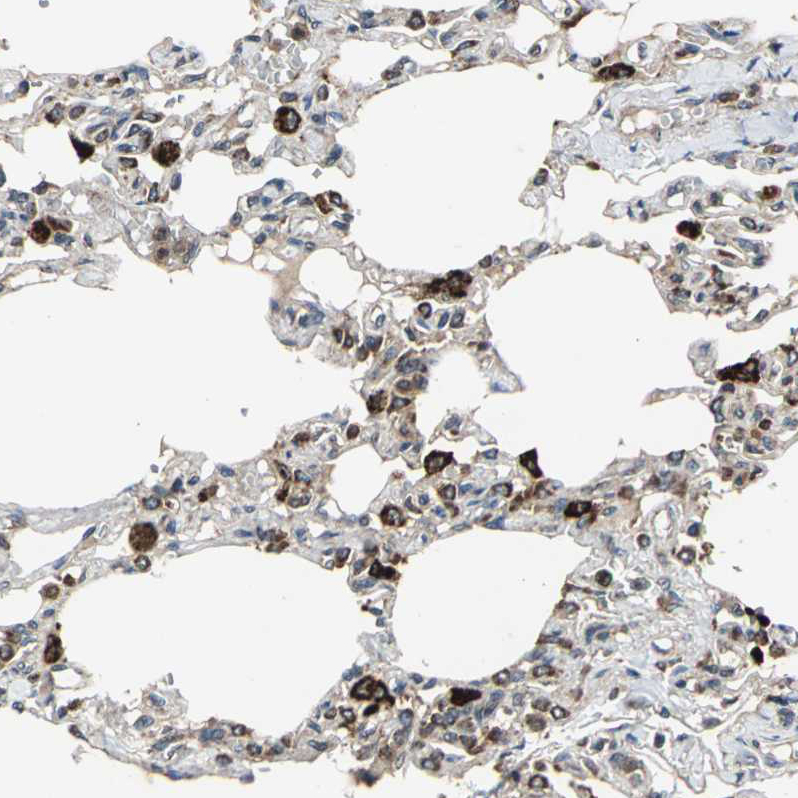

Immunohistochemical staining of human testis shows moderate granular cytoplasmic positivity in cells in seminiferous ducts and leydig cells.